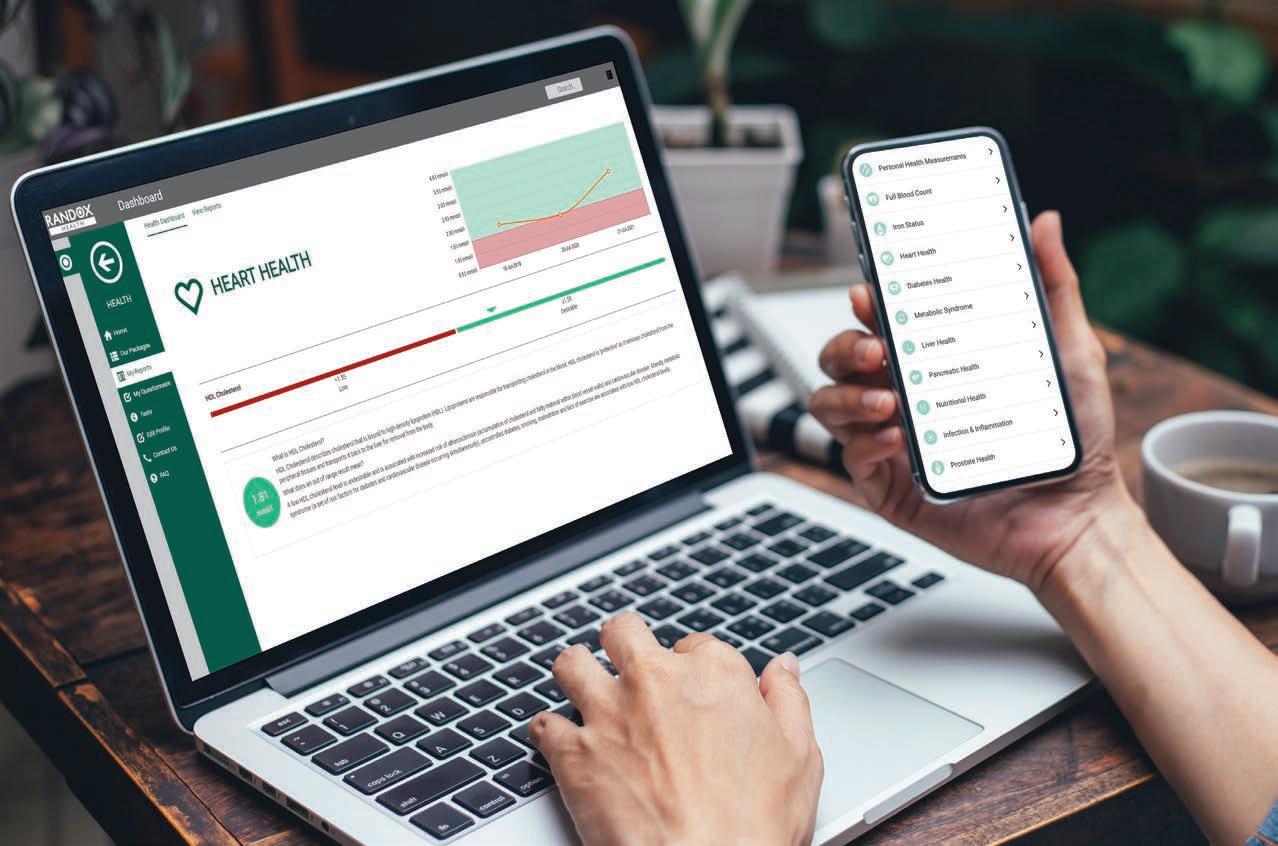

Start the new year with a with a personalised health and wellbeing package from Randox Health

With so much to enjoy in life, protecting your future health is crucial, but keeping track of your health isn’t always easy to do. Faced with time pressures across work and social lives, it can become all too easy to let our health slide.

Why not start your journey towards a healthier New Year with one of our personalised, private health packages. With access to real-time insights on your current health and future health risks, you are empowered to make positive lifestyle changes to help prevent or delay illness.

Regular review of your health is key to understanding and maintaining it. With a new year signalling a fresh

start, there has never been a better time to take control of your health.

Our popular Everyman/Everywoman health programme includes two full health checks six months apart to help you track and improve your health data. Up to 150 data points linked to key health areas are measured during each visit. A personalised health plan summarising your results is then provided, as well as a follow-up consultation with a scientific expert.

Our elite Signature health package has been curated to focus on your full-body wellbeing with a specific emphasis on areas of your health that are important to you. Included within the package are two full health checks six months apart, measurement of up to 350 data points including tumour markers and digestive health, three private GP consultations,

access to genetic testing, an ECG, bowel health at home test, biometric analysis and private prescriptions/referrals if required.

In addition to our full-body health checks, a range of dedicated health checks are available for key health concerns including hormonal health, long Covid, heart health, digestive health, nutritional health, and AMH.

Our range of genetic tests are available to identify risk of inherited conditions including cancer, cardiac conditions, lactose intolerance, and coeliac disease.

Diagnostic testing is key to understanding your physical and mental wellbeing. Whether you want to understand a specific health concern, or help track and improve your current health, Randox Health is for you.

With clinics nationwide, it’s never been easier to take control of your health.

Use code HEALTH22 for 10% o all health packages. Start your journey today by visiting randoxhealth.com